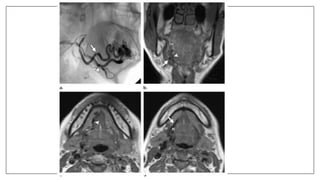

MR Sialography

• MR-Si is a noninvasive method of imaging the ductal system of

submandibular gland and parotid gland.

• This MR technique has the potential to provide a comprehensive

examination for the detailed anatomic assessment of the major salivary

glands.

• The patient’s salivary secretion is used as contrast agent, method of

examination based on a basic principle of usingT2-weighted sequence for

monitoring liquids.

• Its superior properties also include its capability of displaying the duct

diameter in its actual value due to the nonuse of the contrast agent.